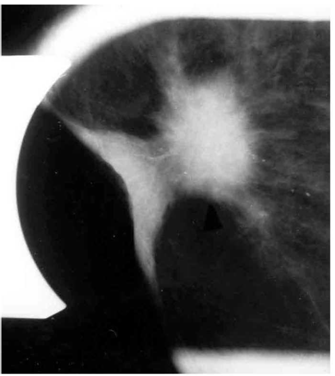

לאחר ביצוע צילומי ממוגרפיה בתנוחות קרניו-קאודלית וצדדית אמיתית, ממקמים את הנגע החשוד באמצעות פלטה עם חורים מרובים, שדרכם ניתן לראות את הנגע (תצלום 26.12).

לאחר החדרת המחט לחור שבו נראה הנגע, מבצעים צילומי ממוגרפיה חוזרים כדי לוודא את מיקום המחט (תצלום 27.12).

לתוך המחט מכניסים חוט מתכתי בעל וו בקצהו, וזה נתפס ברקמת השד. מוציאים את המחט ומקבעים את חוט המתכת אל דופן בית החזה עד למועד הניתוח (תמונה 26.12).

כיום מקובל להכניס מספר סימונים על ידי תיל לסימון מרחב הנגע בשד ולא רק את מרכזו, ובכך להגדיל את הסיכוי להוציאו בשלמותו. לאחר הביופסיה מבצעים צילומי ממוגרפיה של רקמת השד שהוצאה, ומוודאים שהנגע אכן הוצא בשלמותו (תצלום 28.12).